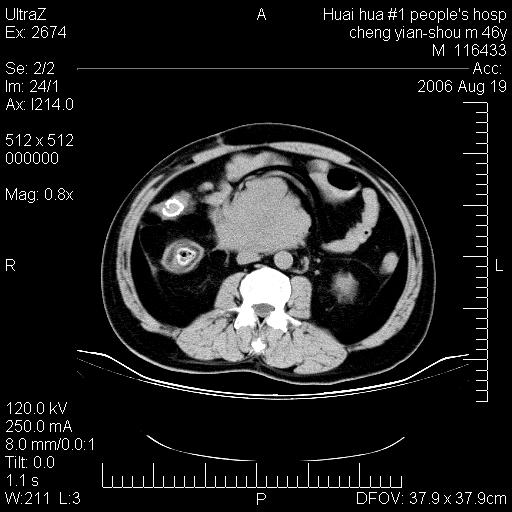

患者,男,46y。腹痛2月,消瘦。

十二指肠水平段占位,考虑间质瘤或平滑肌瘤。

肿块较大,腹膜后占位,境界欠清,周边脂肪密度较高呈条状影,有没有脂肪肉瘤可能,

缺少完整的三期图像。考虑肠系膜脂膜炎mp(肿块型)。

十二指肠水平段占位,考虑间质瘤。

首先考虑小肠间质瘤。

十二指肠水平段软组织密度占位,考虑间质瘤可能性大。

腹膜后占位,境界欠清,考虑来源于十二指肠病变,间质瘤或平滑肌肉瘤可能性大。建议活检。

手术病理结果:原发性小肠恶性淋巴瘤(primary gastrointestinal lymphoma,pgil)是原发于胃肠的淋巴网织系统的恶性肿瘤,在结外淋巴瘤中居第一位,该病少见,临床无特异性,诊断困难,术前主要依靠影像学诊断。胃肠道本身具有较丰富的淋巴组织,因而胃肠原发性淋巴瘤是结外淋巴瘤最常见的部位,文献报道约占胃肠道恶性肿瘤的1%~4%,其中胃约占50%~70%,小肠约占35%~70%,结肠约占4%~6%。影像检查在pgil的诊断及分期中有重要的作用,ct是很有价值的检查方法。

胃肠淋巴瘤病理特点:胃肠道原发性淋巴瘤起源于胃肠壁固有层和黏膜下层的淋巴组织即胃肠粘膜相关淋巴组织(malt),多为粘膜相关淋巴瘤。病理上通常为非霍奇金淋巴瘤,且决大多数来源于b淋巴细胞,很少见于霍奇金淋巴瘤。胃肠原发淋巴瘤比胃肠道癌的发病率要低的多,最常见于胃,其病因可能跟幽门螺杆菌感染有关。幽门螺杆菌能引起胃粘膜损害,引起炎性及免疫反应,淋巴细胞聚集并形成滤泡,可影响胃的正常生理功能,导致胃淋巴瘤的发生。单纯性小肠淋巴瘤是常见好发于回盲末端,受累的肠段较长,可单发、多发,甚至累及整个小肠。原发性大肠淋巴瘤罕见,以直肠和盲肠最多见。病变大体观可表现为胃肠腔内外的肿块,也可表现为从黏膜下到浆膜面肠壁的纵向浸润,并且常常伴有肠系膜淋巴结肿大。任何情况下,肿瘤几乎总是导致一定程度的肠壁增厚,可对称或不对称,病变与正常组织间常无明确分界,肠腔可狭窄、正常或动脉瘤样扩张,后者主要是肿瘤在肠壁内浸润,破坏肠壁内植物神经丛所致。以上改变成为ct检测病变的病理基础。

肠道淋巴瘤的ct表现分为4类

1) 壁内浸润型, (2)多发结节型, (3)肠系膜受累伴腔外肿块型(本型就是),(4)肿块型。